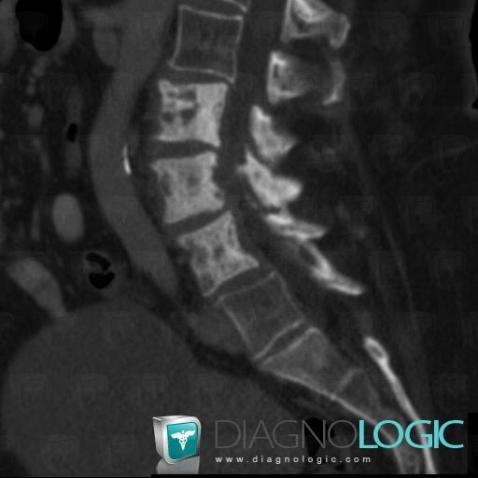

Metastasis, Vertebral body / Disk, CT

Here is the specific information in the key image above:

- Diagnosis Metastasis, Location(s) Vertebral body / Disk, with gamuts Lytic lesion in a vertebra